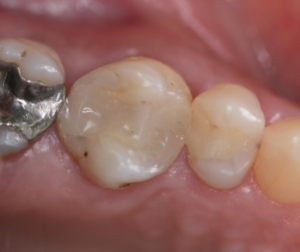

Vista oclusal inicial do elemento 16.